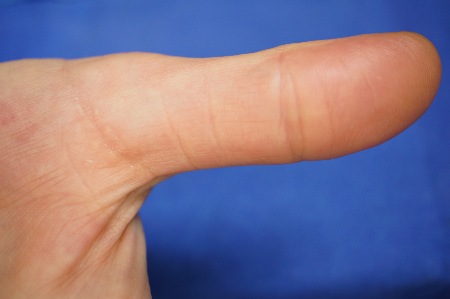

Fortgeschrittenes Karpaltunnelsyndrom mit trockener, rissiger Haut der ersten 3 Finger. Hautcreme befand sich immer in der Handtasche der Patientin

Fortgeschrittenes Karpaltunnelsyndrom mit trockener, rissiger Haut der ersten 3 Finger. Hautcreme befand sich immer in der Handtasche der Patientin